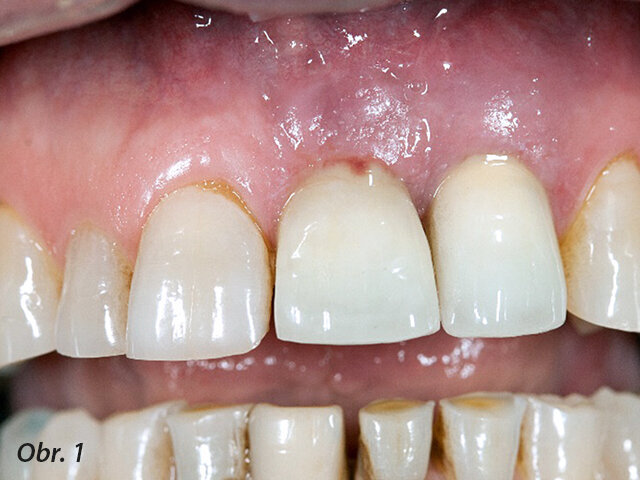

Pacient, 59 let, se dostavil do ordinace a stěžoval si na drobný exsudát u zubních implantátů ve frontální oblasti (obr. 1). Při úvodním vyšetření odhalila sondáž hluboký cirkulární chobot kolem implantátů. Mobilita implantátů však přítomna nebyla. Podezření potvrdilo radiografické vyšetření, které odhalilo pokročilou periimplantitis u nedávno zavedených implantátů (obr. 2).